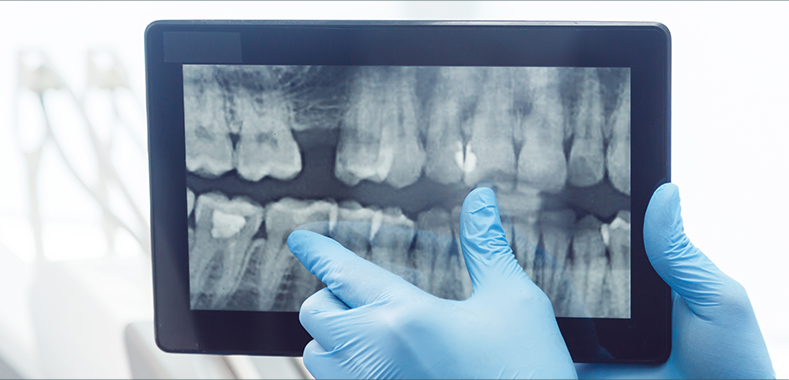

POINT 04

서울미드림치과의 환자 안전 제일의 감염관리 원칙 6